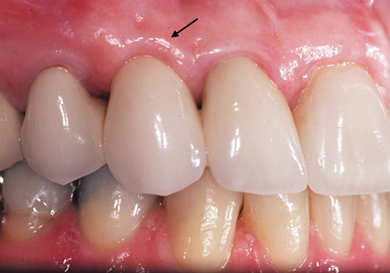

It is essential that an ovate pontic be convex in all dimensions. However, with the traditional "egg in the nest" shape, the gingival marginal tissue over the facial aspect of the pontic is commonly rolled rather than knife edged, which can result in a shadow (Figure 1) and give away that it is a pontic rather than a natural tooth. Therefore, the critical issue isn't the shape of the intaglio surface of the pontic but rather the emergence profile of the pontic on its facial surface. Where the facial aspect of an ovate pontic emerges from the soft tissue, it should have the same contour as a natural tooth. Therefore, it should not be rounded. The facial aspect of an ovate pontic should have a flat surface that goes approximately 1.0 mm under the gingival crest before it starts to become rounded (Figure 2). The shape of the rounded surface of the pontic is determined by the thickness of the ridge in the created site. It will be more round for a thick ridge and more pointed for a thin ridge.

(1.) The gingival marginal tissue over the facial aspect of an ovate pontic with an

Figure 1